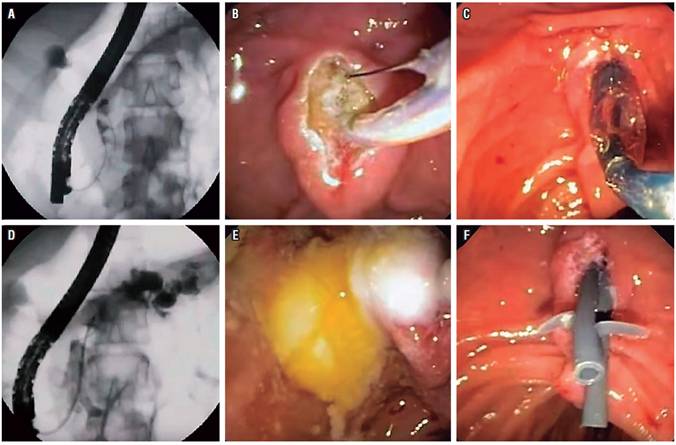

Los cálculos del ducto pancreático son concreciones biominerales que pueden obstruir los ductos pancreáticos. Esto puede resultar en incremento de la presión del ducto pancreático activando un proceso inflamatorio que provoca fibrosis. El objetivo de la terapia endoscópica en pacientes con enfermedad calculosa es aliviar la obstrucción con la remoción de los cálculos 15 (Figura 1).

Con los años, las técnicas para fragmentar y eliminar los cálculos ductales pancreáticos han evolucionado 16. Estas técnicas pueden requerir un acceso intraductal como la litotricia mecánica, litotricia electrohidráulica y litotricia guiada por láser; o una intervención extracorpórea como la LEOC.

La litotricia mecánica intraductal, que se realiza mediante un litotriptor mecánico por vía endoscópica, es técnicamente desafiante con una alta tasa de complicaciones y actualmente rara vez se usa. La litotricia electrohidráulica se realiza bajo visualización pancreatoscópica directa utilizando un sistema endoscópico madre-hijo y tiene la ventaja de suministrar energía a un área focalizada de los cálculos 17. Aunque haya modificaciones técnicas que evolucionan con el tiempo, como el uso de un solo operador del SpyGlass y litotricia con láser de holmio, los estudios en la literatura son limitados 18. Además, la disponibilidad por costos y experticia de los operadores de estas técnicas impide la utilización generalizada.

La LEOC es actualmente la modalidad de primera línea para tratar cálculos ductales pancreáticos obstructivos grandes (>5 mm) dolorosos, particularmente para aquellos localizados en las regiones de cabeza y cuerpo 6. El objetivo es reducir los cálculos a fragmentos menores de 3 mm. Las piedras fragmentadas generalmente se eliminan con una CPRE y esfinterotomía pancreática después de la LEOC. Un stent ductal pancreático concomitante se puede utilizar en presencia de una estenosis local.

La cirugía derivativa es una alternativa para el manejo del dolor y lograr la descompresión de los ductos, y se compara favorablemente con la endoterapia sin LEOC. Sin embargo, debido a la morbilidad asociada con la cirugía, como la cirugía de Frey (Figura 2), esta se reserva generalmente para pacientes en quienes han fallado los tratamientos no quirúrgicos 19.